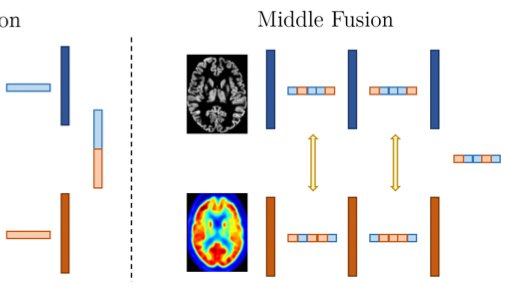

Is a PET all you need? A multi-modal study for Alzheimer's disease using 3D CNNs deepai.org/publication/is… by Marla Narazani et al. including Christian Wachinger #NeuralNetwork #ComputerVision